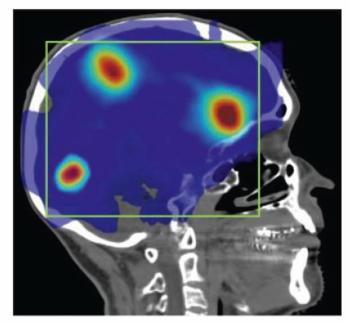

In a cohort of 85 patients with biomechanical recurrence of prostate cancer and PSA values less than 2 ng/mL, positive findings on PET imaging with PSMA-18F DCFPyL led to treatment changes in the majority of patients who had negative findings on conventional imaging, according to new research presented at the SNMMI conference.